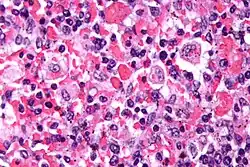

Die Hämophagozytose ist in der Zellbiologie eine Sonderform der Phagozytose. Letztere ist eine Form der Endozytose und bezeichnet im Allgemeinen die Aufnahme von Zellen und sonstigen Partikeln in das Zytoplasma von anderen Zellen. Für die Hämophagozytose im Speziellen ist die Aufnahme von Blutzellen (Erythrozyten und Leukozyten) oder deren Bestandteilen charakteristisch. Diese „einverleibten“ Zellen und Zellbestandteile können in histologischen Präparaten nachgewiesen werden. Bei den aufnehmenden Zellen handelt es sich meist um Zellen, die als Makrophagen bezeichnet werden. Auch hier gibt es wiederum Untergruppen wie zum Beispiel Histiozyten. Sind vor allem Erythrozyten im Zytoplasma der phagozytierenden Zelle nachweisbar, dann wird auch von Erythrophagozytose gesprochen.

Hämophagozytose kommt in größerem Rahmen typischerweise bei Vorliegen einer hämophagozytischen Lymphohistiozytose, auch Makrophagenaktivierungssyndrom genannt, vor. Aber auch nach Bluttransfusionen, im Rahmen von Autoimmunerkrankungen oder einer Sepsis kann Hämophagozytose nachweisbar sein.